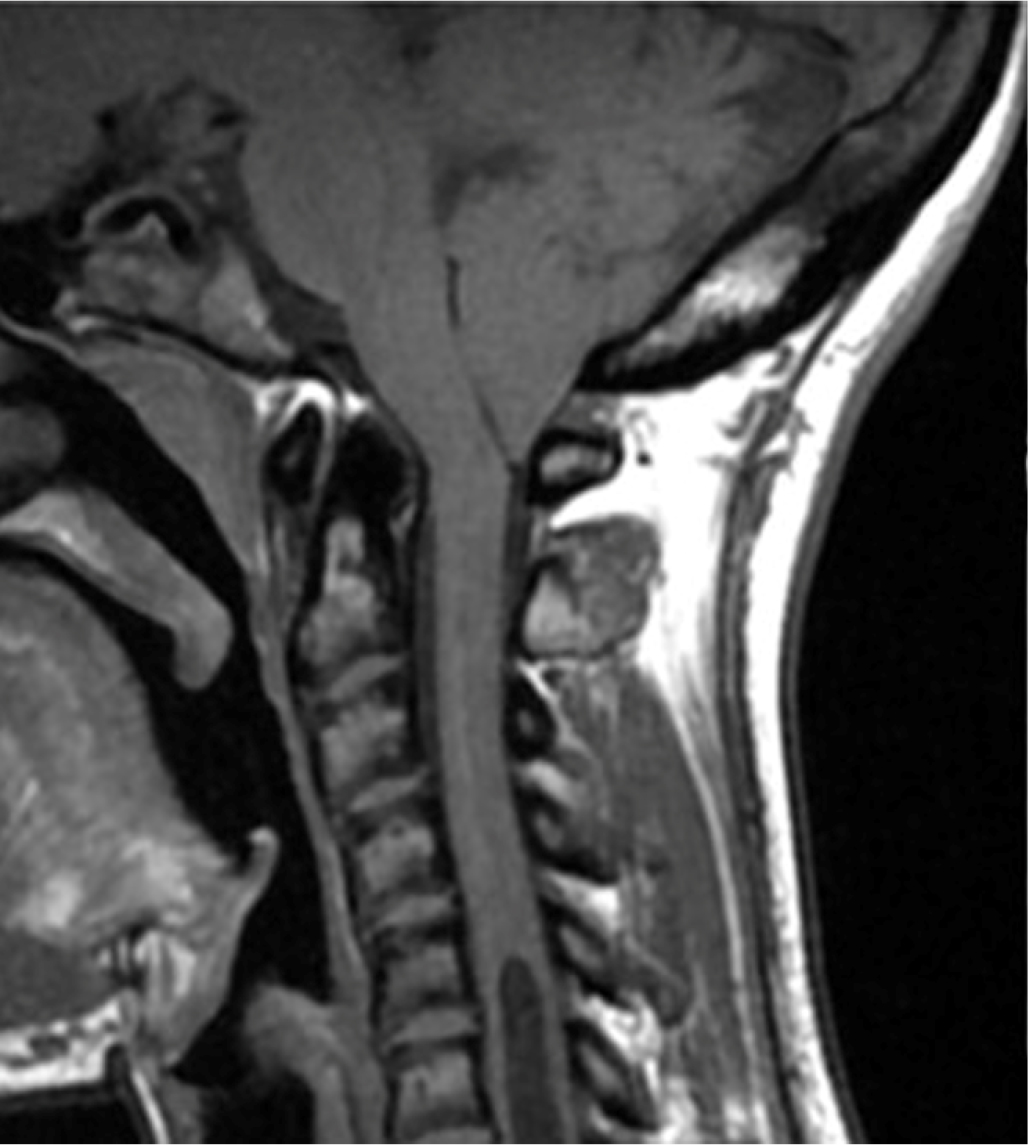

An Arnold-Chiari type 1 malformation was diagnosed by MRI with cerebellar tonsils that engaged in the conjugation frame (for about 3 mm). Furthermore, the medullary cord at the level of the soma of C6 showed a modest extension of the ependymal canal of the syringomyelia type with clinically relevant cephalic expansion (Fig. 4). The patient chose to postpone the indicated surgical procedure.

Fig. 4 - Magnetic resonance imaging of Arnold-Chiari type 1 malformation in case 4.